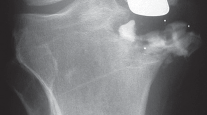

التصوير الطبي ضروري لتأكيد التشخيص وتحديد مدى تلف المفصل:

-

الأشعة السينية العادية (Plain Radiographs):

- المنظر الأمامي الخلفي (AP): يُظهر الركبة من الأمام.

- المنظر الجانبي (Lateral): يُظهر الركبة من الجانب.

- المنظر الخلفي الأمامي المثني (PA Flexed): يسمح بتقييم أفضل للجزء الخلفي من الركبة وقد يكشف عن تغيرات أكبر في الحجرة الخلفية الوحشية.

- منظر شروق الشمس (Sunrise/Patellofemoral): لتقييم المفصل الرضفي الفخذي.

- الأشعة السينية الطويلة للطرف السفلي بالكامل (Full-length standing radiographs): من الورك إلى الكاحل، وهي مفيدة جدًا، خاصة إذا تم استخدام تقنيات الملاحة الحاسوبية. تُظهر هذه الأشعة المحاذاة الكلية للطرف السفلي.

التصوير بالرنين المغناطيسي (MRI): يُعد ضروريًا في حالات التنخر العظمي لاستبعاد إصابة الحجرات الأخرى.